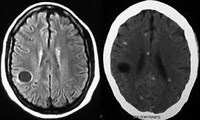

Điều phù hợp, các nghiên cứu dịch tễ học có sử dụng hình ảnh CT scan não (hoặc một số ca dùng MRI), chỉ ra 10-20% ca có ấu trùng sán dây lợn (ATSDL) trong não, hầu hết họ chỉ có một hay vài vết sẹo hóa canxi và không có biểu hiện lâm sàng.

Hình 2

Hầu hết số ca nhiễm trùng ở người thông qua các nghiên cứu dựa trên quần thể tương ứng với các thương tổn canxi hóa.